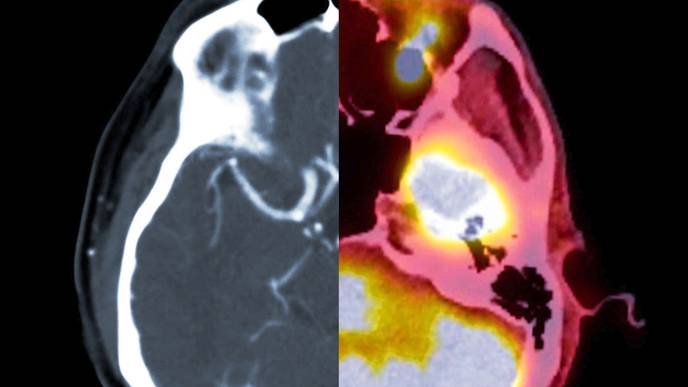

A new study, published in Biological Psychiatry, has revealed that mindfulness meditation engages distinct brain mechanisms to reduce pain compared to those of the placebo response. The study, conducted by researchers at University of California San Diego School of Medicine, used advanced brain imaging techniques to compare the pain-reducing effects of mindfulness meditation, a placebo cream and a “sham” mindfulness meditation in healthy participants.

The study found that mindfulness meditation produced significant reductions in pain intensity and pain unpleasantness ratings, and also reduced brain activity patterns associated with pain and negative emotions. In contrast, the placebo cream only reduced the brain activity pattern associated with the placebo effect, without affecting the person’s underlying experience of pain.